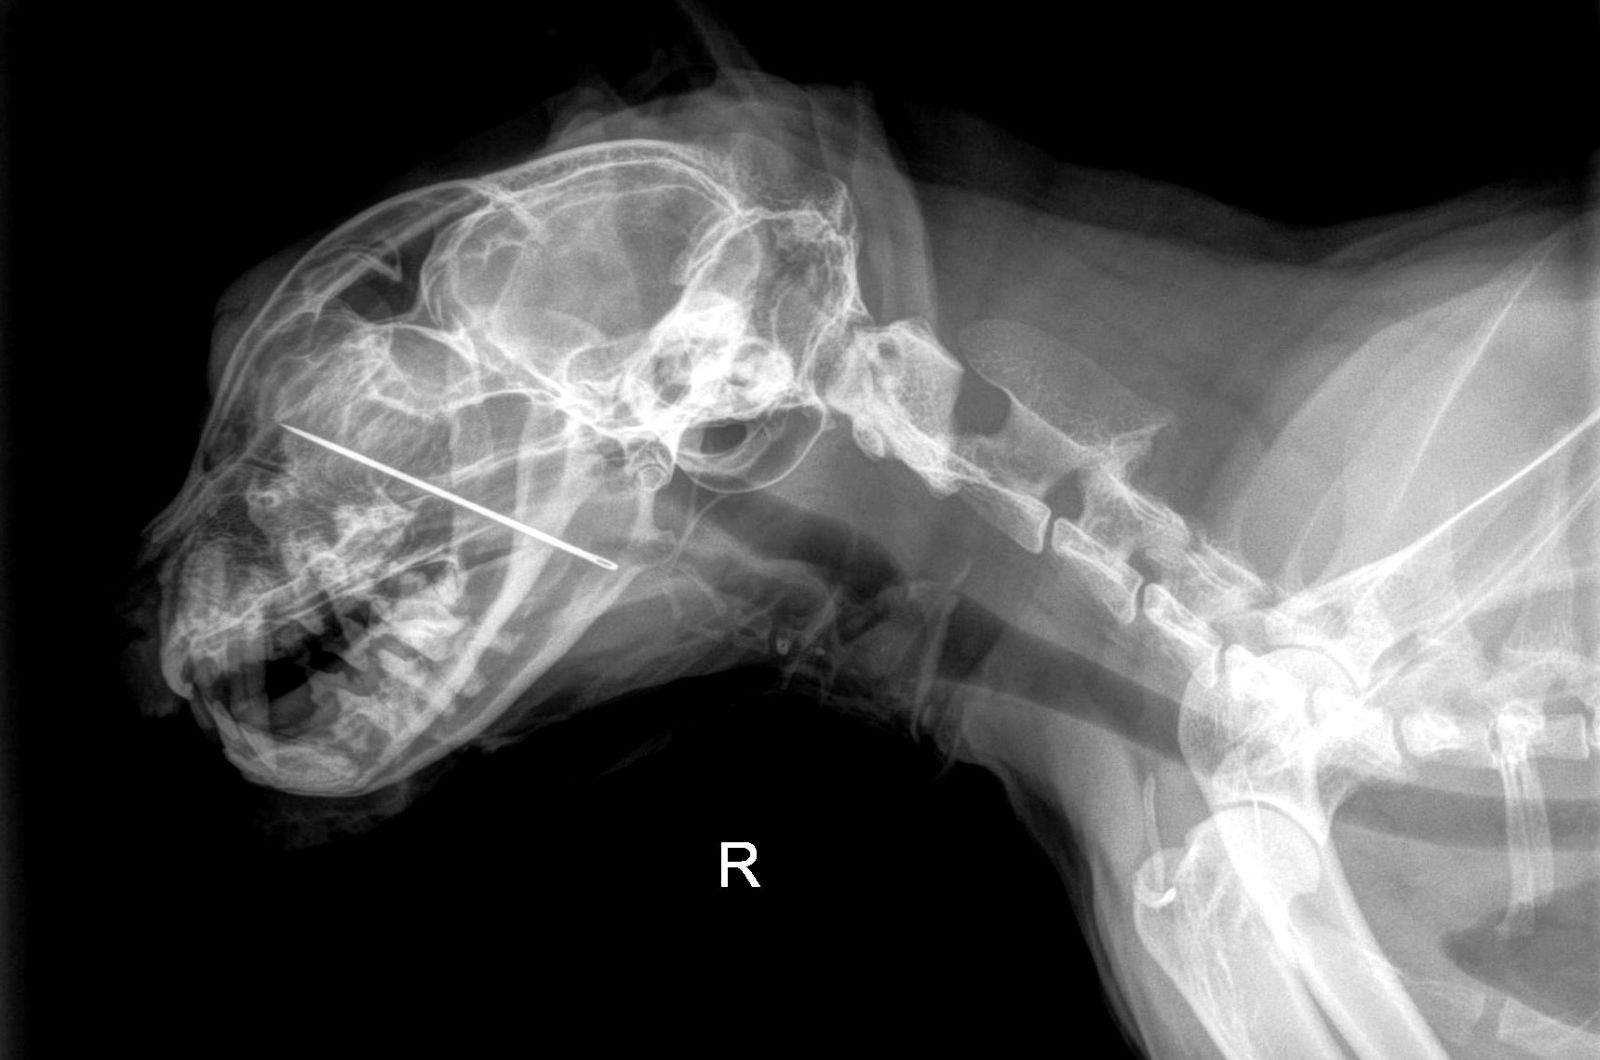

That’s when the shocking discovery was made. An X-ray revealed the sewing needle stuck firmly in his hard palate, extending into his nasal cavity.

It was a sight that made even the experienced staff pause. But the team wasted no time. With precision and skill, they carefully removed the needle before it could cause more damage.